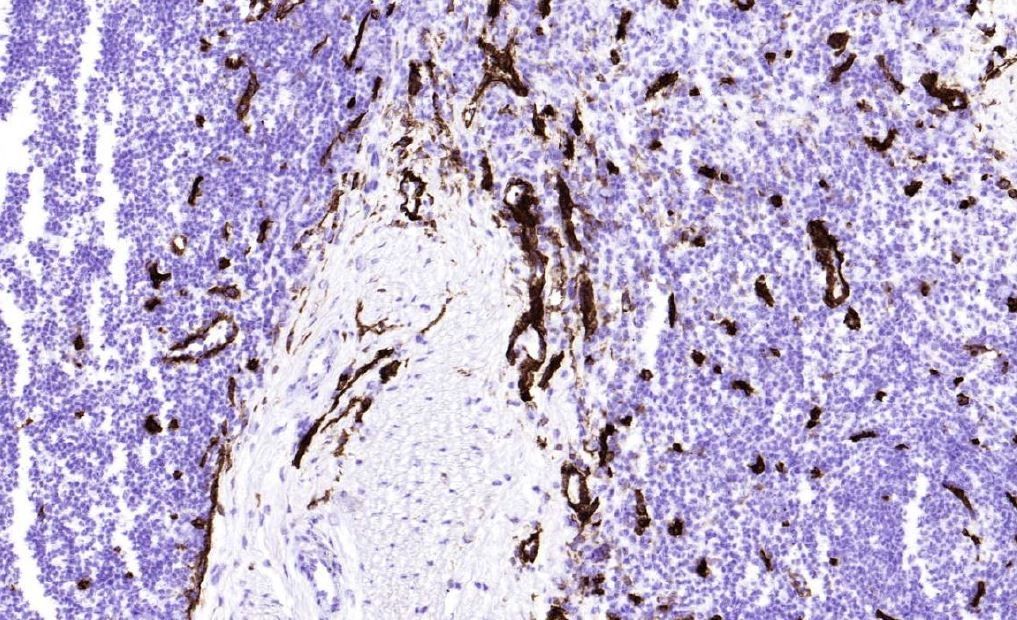

Anti CD36

別品名 GPIV, Fatty acid translocase (FAT), platelet glycoprotein 4, PAS IV, Platelet collagen receptor, thrombospondin receptor, Gene name: CD36

適用 IHC frozen section